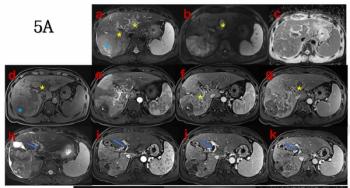

For patients with unresectable hepatocellular carcinoma, a pre-treatment MRI finding of LI-RADS tumor in vein was associated with over an 86 percent lower likelihood of responding to transcatheter arterial chemoembolization (TACE) and targeted immunotherapy.